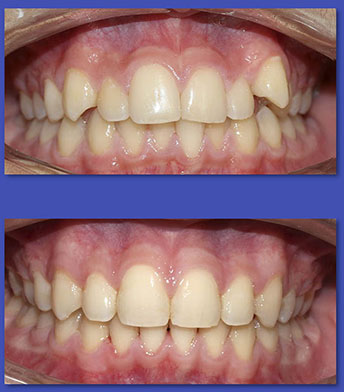

4. ORTODONCIA

La Ortodoncia se encarga del tratamiento de las anomalías de forma,posición,relación y función de las estructuras dentomaxilofaciales. La causa más común para el uso de aparatos de ortodoncia son las malposiciones dentarias o “ dientes chuecos “.

ANTES

DESPUÉS